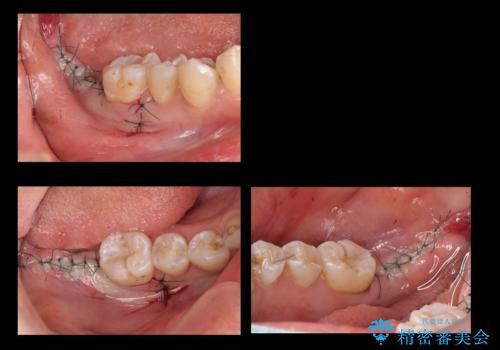

奥歯の歯ぐきからウミが出る 抜歯してインプラントへ

- 奥歯の歯ぐきからウミが出ている、抜歯が必要と他院で言われたとのことでした。

ただし、かかりつけではインプラント治療を行っていないため、病院を探したとのことでした。

抜歯を行い、インプラントを入れていきました。

炎症で骨が少なかった場所には骨補填材を置いています。